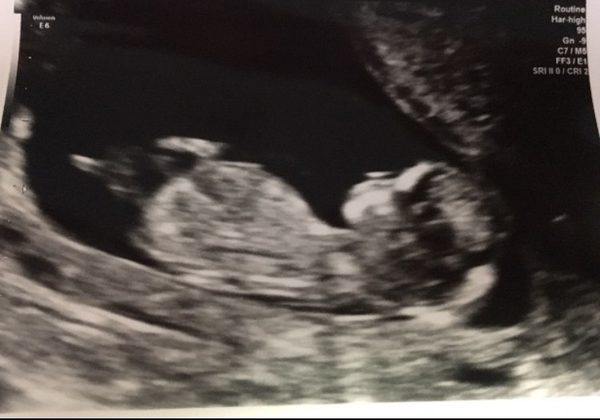

Due in June, 12 week scans happening and coming up!

AFM- we had our 12 week scan this morning and all is very well. We are so, so relieved. I was a blubbering wreck before and during. Measuring 3 days ahead with NT measurement of 1.5mm. And all body parts present. Absolutely over the moon and now cannot wait to share our news on Christmas Day with close family Smile

Tomato I can't see your nub, but I am no expert. Looks like a girlie head to me.